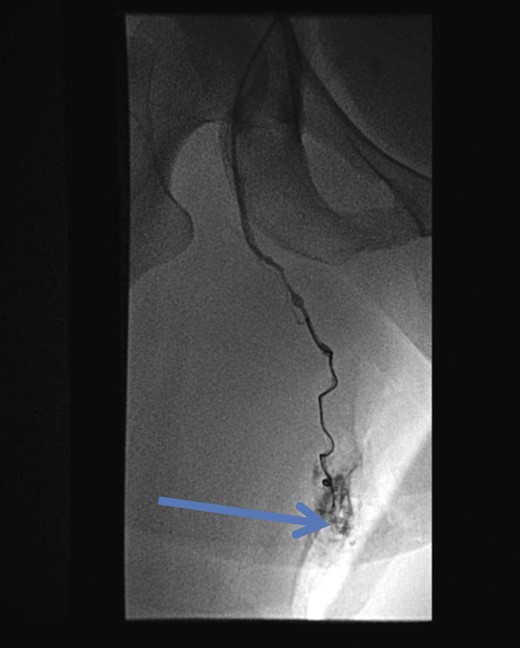

The superficial external pudendal vein was embolized with 1% sodium tetradecyl sulphate and then coiled through a contralateral puncture under fluoroscopic guidance (Figs 3 and 4). The procedure went uneventfully with successful obliteration of the communicating thigh veins to vulval varices (Fig. 5) and the patient was discharged home the same day.

Pre-embolization fluoroscopy showing communication of thigh veins to vulval varices (blue arrow).